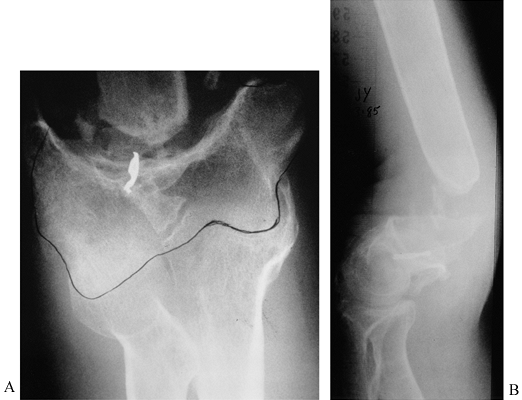

frequently leads to shortening and loss of bone substance (Fig. 27.10 and Fig. 27.11). Reconstruction

![]() |

|

Figure 27.10.

AP and lateral radiographs of a 42-year-old man with a supracondylar nonunion of the humerus. He had only a 40° arc of motion in the elbow joint and had been using this pseudarthrosis for motion. Note the resorption of the proximal fragment and the size mismatch at the fracture site. See Figure 27-11 for management of this problem. |